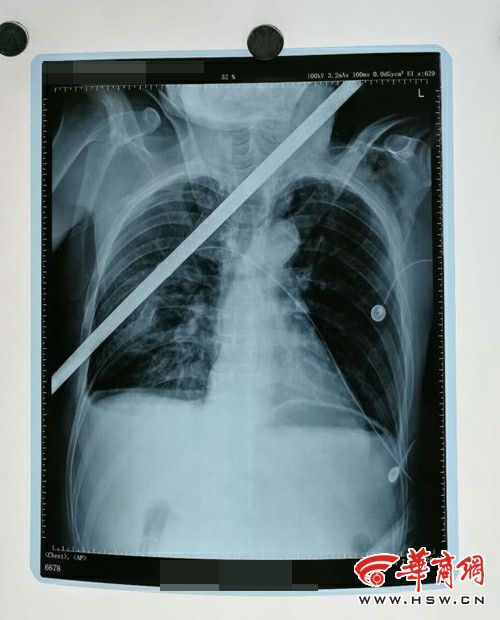

咸阳男子被高空坠落钢筋插入身体 医护人员和

500x620 - 45KB - JPEG